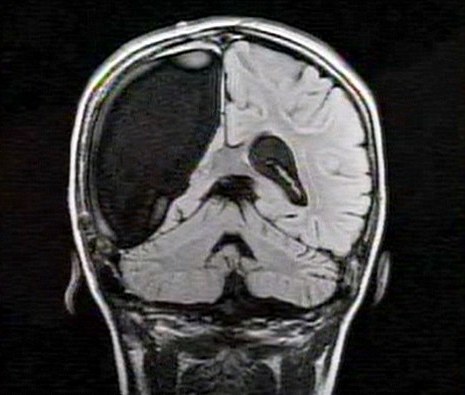

中新網3月26日電 據英國媒體26日報道,一名9歲的英國女孩在經歷了右腦切除手術后奇跡康復,令醫生和家人無比震驚。

報道稱,現年9歲的卡梅倫•莫特在手術中切除了她整個右半邊的大腦,而在經歷如此重大的手術后能迅速康復,莫特的奇跡也讓醫生和她的家人驚嘆不已。年幼的莫特也沒有因為病癥而放棄對夢想的追求。

卡梅倫莫特在3歲那年患上一種被稱作大腦功能紊亂“拉斯穆森”綜合癥,這種病癥誘發患者的無序暴力行為和嚴重的癲癇。醫生建議,治療這種病癥只能通過嘗試消除引發此癥狀的大腦組織。而手術讓莫特失去了幾乎整個半邊的大腦。

據悉,莫特在手術后已經可以跑動和玩耍,她在術后的第四周離開了醫院。醫生表示,雖然右半邊大腦的切除可能會給莫特帶來半身不遂的風險,但孩子剩余的大腦仍具有很強的重組和布線能力。